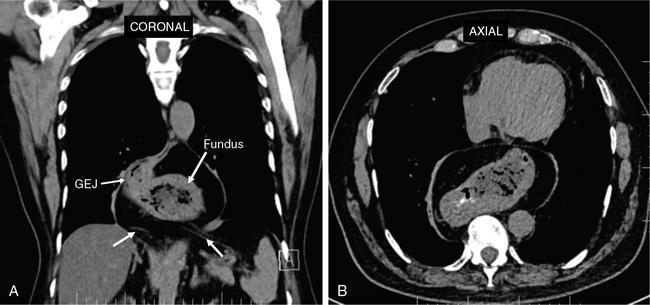

Swarup Nellore, Soumil Vyas, Ujwal Bhure, Ankit Jain, Richa Kothari, Daksh Mehta, Divya Kantesaria, Disha Lokhandwala, Karthik Ganesan The stomach is the most dilated portion of the gastrointestinal tract positioned between the oesophagus and the small intestine occupying the epigastrium, left hypochondrium and umbilical regions of the abdomen performing a multitude of functions including storage and mixing of food and controlling the passage of food into the intestine. Anatomically, the stomach is divided into the following parts (Fig. 8.2.1): the gastric cardia is the portion immediately adjoining the oesophageal opening into the stomach. The fundus is the dome-shaped part above the horizontal plane of the cardiac orifice which undergoes receptive relaxation and is the site of the autonomic pacemaker. The body is the largest part of the stomach extending from the cardiac orifice to the level of incisura angularis (notch like bend in the mid lesser curvature) containing majority of parietal cells (which secrete hydrochloric acid), chief cells (pepsinogen) and enterochromaffin-like cells (ECL). The pylorus is the tubular distal portion of the stomach which is further divided into the gastric antrum and pyloric canal. The pyloric antrum containing G-cells producing gastrin extends from the incisura angularis up to the pyloric sphincter which is an anatomical sphincter formed by concentric thickening of the circular muscle coat and encircles the narrow-slit like pyloric canal. The left dome of diaphragm and oesophagus lie superior to the stomach while the greater omentum and pancreas lie inferiorly. Spleen and liver lie on either side laterally while the transverse mesocolon is located inferolaterally. Diaphragm, greater omentum, left lobe of liver and anterior abdominal wall are anteriorly related to the stomach and contents of lesser sac including pancreas, spleen, splenic artery, transverse mesocolon, left kidney and adrenal gland lie posteriorly. The stomach is embryologically derived from the primitive foregut and is suspended anteriorly by the ventral mesogastrium and posteriorly by the dorsal mesogastrium. During development as the stomach rotates, the peritoneum grows and condenses to form perigastric ligaments, which contain blood vessels, lymphatics, lymph nodes, nerves and fat. The liver forms in the ventral mesogastrium, which develops into the falciform ligament, gastrohepatic ligament (GHL) and hepatoduodenal ligament (HDL). The spleen and pancreas form within the dorsal mesogastrium, which fuses with the posterior abdominal wall to form the gastrocolic ligament (GCL), gastrosplenic ligament (GSL) and splenorenal ligament (SRL). The perigastric ligaments are identified anatomically by the vessels contained in them (Fig. 8.2.2). The gastric cardia and lesser curvature of the stomach are attached to the inferior surface of liver by the lesser omentum by the gastrohepatic ligament respectively which contains the left and right gastric vessels. The inferior free edge of the gastrohepatic ligament extends inferiorly as the hepatoduodenal ligament between the porta hepatis and proximal duodenum gastrophrenic ligament extends between the stomach and the left hemidiaphragm. The gastrocolic ligament identified by the left and right gastroepiploic vessels, connects the greater curvature of the stomach to the anterior surface of the transverse colon. This ligament extends inferiorly as the greater omentum which is a double-layered peritoneum forming a drape anterior to the bowel loops. The gastrosplenic/lienogastric ligament bridges the posterolateral wall of the fundus and greater curvature along the proximal body of the stomach to the splenic hilum and contains the short gastric vessels. The gastrosplenic ligament is contiguous with the lienorenal ligament and both these structures constitute the lateral boundary of the lesser sac. Macroscopically the stomach shows a thick vascular mucosal lining in the form of longitudinal folds called gastric rugae. Microscopic layers of the stomach include mucosa, submucosa, muscularis externa and serosa. The mucosa includes surface mucus cells with simple columnar epithelium, gastric pits, gastric glands, lamina propria and muscularis mucosa. Submucosa includes connective tissue with submucosal Meissner’s plexus. Muscularis externa comprises three smooth muscle layers (longitudinal, circular and oblique) and Auerbach myenteric plexus. The outermost layer called serosa consists of loose connective tissue and visceral peritoneal lining. The arterial supply of stomach is constituted by the branches of celiac artery predominantly in the form of two anastomotic arcades along the lesser and greater curvature. Left gastric artery, a direct branch of the celiac trunk supplies the upper part of the lesser curvature while the lower part is supplied by the right gastric branch of the common hepatic artery arising at the upper border of pylorus. The left gastroepiploic artery, a branch of splenic artery, supplies the upper part of greater curvature and the inferior portion is supplied by the right gastroepiploic artery which is a branch of the gastroduodenal artery. The fundus additionally receives few small short gastric branches from the splenic artery. The veins follow the arteries in their nomenclature. Left and right gastric vein show direct drainage into the portal vein. The splenic vein derives flow from the short gastric and left gastroepiploic vein whereas the right gastroepiploic vein drains into the superior mesenteric vein. Pylorus can be surgically delineated by the prepyloric vein of Mayo lying on its anterior surface. Intrinsic nerve supply consists of the myenteric plexus of Auerbach and submucosal plexus of Meissner. Extrinsic nerve supply consists of sympathetic and parasympathetic components. Sympathetic nerve supply arises from T5 to T9 spinal cord segments supplying the celiac plexus via the greater splanchnic nerve. The plexuses then travel along the respective branches of celiac artery supplying the stomach. Parasympathetic nerve supply is derived from oesophageal plexus of vagus dividing into two vagal trunks. Right (posterior) vagus gives off the posterior gastric branch also called the criminal nerve of Grassi supplying the cardia and fundus of stomach. Right vagus then gives off a celiac branch and continues along lesser curvature of stomach as the posterior gastric nerve of Latarjet supplying the antrum, body and pylorus. Left (anterior) vagus gives off a hepatic branch then continues along the lesser curvature as the anterior nerve of Latarjet supplying the antrum, body and pylorus. Crow’s feet innervation to antropyloric area are important surgical landmarks preserved during highly selective vagotomy receiving branches from both major nerve trunks (anterior and posterior) at the incisura angularis. Anatomical lymphatic drainage is divided into three areas. Area I is the superior two-thirds of stomach draining via the nodes along left and right gastric vessels into the aortic nodes. Area II includes the right two-thirds of the inferior one-third which drains through the nodes along right gastroepiploic vessels via the subpyloric nodes into aortic nodes. Area III includes left one-third of greater curvature draining via short gastric and splenic nodes into suprapancreatic nodes and ultimately into aortic nodes. Gastric lymph node stations are divided into 4 levels with 16 lymph node stations: Paraesophageal nodes below the diaphragmatic hiatus (17) and above the diaphragmatic hiatus (18) are also included. The stomach first appears as a fusiform dilatation in the distal endodermal foregut in the 4th week of embryonic life. The dorsal and ventral mesogastrium suspend the developing stomach to the respective abdominal walls. Preferential growth along the dorsal border of the developing stomach leads to the formation of a convex dorsal border (greater curvature) and a concave ventral border (lesser curvature). The stomach subsequently undergoes a sequence of rotations. The first (90 degrees) clockwise rotation occurs around the longitudinal axis which brings the lesser curvature to the right and greater to the left. This rotation also brings the dorsal mesogastrium towards the left and ventral to the right creating a space behind the stomach called as the lesser sac or omental bursa. The second clockwise rotation occurs around the anteroposterior axis, with the caudal or pyloric part moving upwards and to the right while the cephalic or cardiac portion moves towards the left and slightly downward causing the stomach to assume its final anatomic position. This rotation causes the dorsal mesogastrium to bulge downwards and grow further to eventually become a double-layer apron called the greater omentum. The developing liver divides the ventral mesogastrium into the falciform ligament extending from the ventral abdominal wall to the liver with its lower free edge forming the ligamentum teres, the visceral peritoneum surrounding the liver and the lesser omentum with its two parts – the hepatogastric ligament and hepatoduodenal ligament. The dorsal mesogastrium gives rise to the redundant greater omentum, gastrocolic ligament, gastrosplenic ligament and lienorenal ligament. These perigastric ligaments help us in deciphering patterns of the spread of gastric malignancies and in taking decisions regarding their management and prognostication. These will be further explained in detail under the section of gastric malignancies. An abdominal radiograph is often the initial imaging test for evaluation of acute abdominal pain. The gastric bubble is seen below the left hemidiaphragm in situs solitus. Presence of gastric outlet obstruction may show a distended stomach with gasless small bowel. Hollow visceral perforation is diagnosed by free air seen under domes of diaphragm. Also, the presence and position of various tubes like the nasogastric tube can be confirmed using a radiograph. A fluoroscopic upper gastrointestinal (GI) examination is the radiological study of oesophagus, gastro-oesophageal junction, stomach, duodenum up to duodenojejunal junction by oral administration of contrast. Barium sulphate is a good contrast medium for GI studies as it is radio-opaque, non-absorbable, inert to tissues and can be used for double-contrast studies. Patient should be nil by mouth at least 4 hours prior to the examination. In a single contrast examination, the emphasis is on mucosal relief, luminal distention with contrast material and compression. In the erect position, a small amount of contrast is given to swallow while the oesophagus is visualized under fluoroscopy. The table is then made horizontal and the patient is rotated in a clockwise manner as seen from the foot end of the patient, thus ensuring good coating of the stomach mucosa. Mucosal relief images are then obtained in supine and prone positions to demonstrate the mucosal fold pattern and possible filling defects. After giving some more contrast, the patient is turned oblique with the right side dependent and spot images of the duodenal cap and C loop are taken both in distended and empty states. The patient is again positioned erect and more images of duodenal cap and loop are taken. Further contrast is given to optimally distend the lumen and assess for possible contour abnormalities, wall rigidity and strictures. Compression techniques help assess for filling defects and lesions, in the compressible areas of the stomach. Images are taken in multiple positions – supine, prone, right anterior oblique, right lateral, left posterior oblique in recumbent and right anterior oblique in erect position. Gastric peristalsis and emptying can be observed at fluoroscopy. Advantages of the single contrast technique are that it can be performed quickly, well-tolerated and requires less patient cooperation as compared to double-contrast studies. It can even be performed in physically debilitated patients. Barium is contraindicated in suspected cases of perforation, aspiration, fistula or recent GI biopsy. Single contrast examination can be performed using water-soluble iodinated contrast media in these cases and immediate postoperative patients. Earlier, ionic contrast like Gastrograffin was used. However, due to its high osmolarity, nowadays, non-ionic contrast is preferred as it causes less electrolyte imbalance due to its low osmolarity. Also, it delineates the GI tract very well due to less dilution. Double-contrast studies provide better evaluation of the mucosa than do single-contrast studies. Here, the emphasis is on coating the mucosa with barium and distending the lumen with gas. A well-performed double-contrast study is biphasic and also incorporates some single-contrast techniques. The initial part of the examination is the same as a single contrast examination to obtain the mucosal relief images. Then, gas-forming powder that produces carbon dioxide within the stomach lumen is given with more barium. With the double-contrast technique, the mucosa is coated with a high-density barium suspension and the lumen distended with gas. The patient is rotated in a clockwise manner as seen from the foot end of the patient, thus ensuring good coating of the stomach mucosa. Spot images of the distended stomach are taken followed by the duodenal cap and loop in oblique right-side dependent position. Patient is brought back to erect position erect and more images of stomach, duodenal cap and loop are taken. Further contrast is given to distend the lumen. Residual fluid or food debris in the stomach impairs stomach coating, and lack of adequate coating may preclude visualization of lesions. In addition, optimal gaseous distention is important as underdistention will cause a false appearance of abnormally thickened, and overdistention can obliterate abnormal folds. With normal gastric anatomy, the gastric fundus is best visualized in the upright left-posterior-oblique position, the body in the supine anteroposterior position and the antral-pyloric region in the supine left-posterior-oblique position. The normal gastric mucosal surface should be smooth on double-contrast studies. Areae gastricae appear as reticular networks of polygonal tufts which, owing to the presence of barium in the narrow intervening grooves, are coated with white lines. These are seen most often in the antrum or body of the stomach but can also be seen in the fundus. Areae gastricae are identified on double-contrast studies in 70% of patients and are seen more often in elderly patients. Polygonal tufts should normally range in size from 2 to 3 mm in the antrum and 3 to 5 mm in the body and fundus. Normal gastric folds are more prominent in the proximal to mid stomach and more undulating along the greater curvature as compared with the lesser curvature. Antral folds should be typically effaced with the double-contrast technique. Gastric cardia is characterized by three or four stellate folds radiating from a central point at the gastro-oesophageal junction; this is known as the cardiac rosette and is best visualized in the supine right-lateral position. Ultrasonography (USG) is the modality of choice to visualize hypertrophic pyloric stenosis in infants. Although USG does not play much of a role in adults for imaging of stomach due to reflection of sound waves by air, luminal distension with water may enable to identify mucosal – submucosal pathologies and to assess perigastric relationships in pathologies. CT can not only evaluate the location and anatomy of the stomach, but also provide additional information about the relationship of the stomach to surrounding structures. An optimal CT examination of the stomach includes good stomach distension with a well-visualized wall. Gastric distention can be achieved by the oral administration of negative or positive luminal contrast. Positive contrast agents include a 1%–2% barium suspension or a 2%–3% solution of a water-soluble iodinated contrast agent. Water-soluble agents should be used in cases of suspected perforation. Positive agents provide a bright lumen with better identification of luminal encroachment or diverticula but may limit detailed evaluation of gastric wall enhancement. Positive contrast also may not mix well with gastric contents, producing a pseudotumor appearance. On the other hand, neutral or negative contrasts agents, usually water, produce a low attenuation lumen which allows for more detailed evaluation of the gastric wall and its enhancement pattern following intravenous contrast and is preferred for three-dimensional imaging. Multidetector CT with thin collimation allows for postprocessing in any orthogonal plane. The CT data of the stomach can be manipulated to simulate endoscopic images (virtual gastroscopy). This display technique accentuates the stomach wall and folds. Prior to evaluating the stomach with CT, oral contrast is administered at repeated intervals as well as immediately prior to scanning. Multiphasic scanning after intravenous contrast may be employed at 25–35 seconds (late arterial), 55–75 seconds (venous phase) after contrast injection. Normally, the gastric wall may enhance to approximately 120 Hounsfield Units after intravenous contrast administration. The mucosa may enhance more than the relatively lower-attenuation muscularis propria. Abnormal enhancement of the wall can highlight pathologic processes. The CT appearance of the stomach also depends upon the degree of distention. When well distended, the body and fundus is less than 5 mm thick, though the normal antrum may appear slightly thicker. The presence and pattern of wall enhancement, degree and location of wall thickening, and length of an involved segment may be assessed. Comprehensive MRI examination of the stomach and duodenum by the combined use of T2-weighted single-shot and T1-weighted gradient echo (GRE) – with and without fat suppression, and gadolinium-enhanced 3D GRE helps to detect the spectrum of gastric diseases on MRI. These sequences minimize artefacts from bowel peristalsis, increase the sensitivity of detection of peritoneal and serosal disease by suppressing the high signal of intra-abdominal fat, widen the dynamic range of abdominal tissue signal intensities and distinguish between intraluminal bowel contents and bowel wall. The gastric rugae are well seen on T2-weighted single-shot spin-echo images and their enhancement appears as bands of enhancing tissue arranged perpendicular to the external contour of the gastric wall. The normal gastric wall enhances more intensely than other segments of bowel on immediate postgadolinium SGE images. Water is frequently used as an oral contrast agent when imaging the upper GI segment-stomach and duodenum. Noninvasive dynamic study for assessment of gastric motor function and wall motility can also be done using MRI for diagnosis of gastroparesis. Gastric emptying scintigraphy (GES) is a well-established radionuclide procedure to evaluate patients with suspected gastric motility disorder, more so for non-invasive assessment of gastroparesis in patients with symptoms of postprandial fullness, nausea, vomiting, abdominal pain, bloating, early satiety, loss of appetite, as well as weight loss. Gastroparesis, commonly seen in diabetics, is a condition that affects the normal spontaneous movement of the gastric muscles, leading to impairment of gastric motility, because of which the stomach cannot empty itself of food in a normal fashion and time. GES can also provide useful information with regards to assessment of impaired gastric motility in patients with GERD (gastro-oesophageal reflux disease) unresponsive to routine therapy, diabetics with poor glycemic control, and also in patients with colonic inertia who are being considered for colectomy (since benefits of colectomy are mitigated in patients with concurrent impaired gastric emptying). On the other hand, GES is also useful for assessment of rapid gastric emptying (GE), which is a major factor in dumping syndrome, often seen post peptic ulcer surgery, with or without vagotomy. The solid or liquid component of a meal is radiolabelled with a radiopharmaceutical, which is consumed by the patient and subsequently measured gastric radioactive counts by scintigraphy correlate with the volume of the meal remaining in the stomach. Solid-phase GES is used for the evaluation of gastric motility disorder/gastroparesis. Liquid-phase gastric emptying is generally not clinically useful since it is often in the normal range in spite of deranged emptying for solids even with severe gastroparesis. The preferred radionuclide meal for the gastric emptying scintigraphy includes egg-white radiolabelled with 0.5–1.0 mCi of Technetium-99m (99mTc) [approximate caloric value of 255 kcal]. Two large eggs (egg-whites), two slices of bread, fruit jam, water (120 mL approximately), and the radiopharmaceutical (0.5–1.0 mCi of 99mTc–sulphur colloid). For patients allergic, to eggs, alternative meals like oatmeal or Liquid Ensure nutrient supplement can be used. Reporting should include the percentage of radiotracer retained in the stomach at defined time intervals. The normal reference values for comparison are as follows: Grading the severity of the delay in gastric emptying based on gastric retention at 4 hours of the study: Gastro-oesophageal reflux (GER) is a common condition in infants and children, wherein there is reflux of stomach contents into the oesophagus, due to possible incompetence of gastro-oesophageal sphincter, which can lead to development of symptoms like regurgitation, heartburn, cough and dyspepsia. Children can present with recurrent respiratory infections, iron deficiency anaemia and failure to thrive. It is often a self-limited process in infants and children which usually resolves by 12–18 months of age. On the other hand, gastro-oesophageal reflux disease (GERD) is a chronic pathological process which can be troublesome. Scintigraphic evaluation of gastro-oesophageal reflux, popularly known as ‘milk scan’, is an established imaging modality and has sensitivity of 75%–100%. This radionuclide test for gastro-oesophageal reflux is physiological and quantitative and commonly used for diagnosis in neonates and infants. Four hours fasting is preferred. A liquid meal consisting of formula, milk, or orange juice mixed with the radiopharmaceutical is administered either orally or by nasogastric tube. 99mTc–sulphur colloid. Dose: 0.2 to 1 mCi. After administering the liquid meal and allowing burping, the baby is positioned supine under the gamma camera detector head, including chest and upper abdomen in the field of view. A radioactive marker can be placed at the mouth. Anterior serial dynamic planar images are acquired for around 60 minutes with a framing rate of 5–10 seconds per frame. Delayed anterior static image of the chest may be acquired additionally. The acquired frames are reviewed in cinematic display for visual estimation and to look for reflux of the radiotracer into the oesophagus. Reflux is seen as distinct spikes of radiotracer activity into the oesophagus. For quantitative estimation, the volume of each episode of reflux, frequency of episodes and rate of reflux clearance from the oesophagus are taken into consideration. Percentage of reflux is calculated by drawing an ROI over the oesophageal spike of radiotracer activity and the counts are calculated and expressed as a fraction of the gastric activity counts. Values greater than 5% are suggestive of reflux. Semiquantitative evaluation grades each reflux event: Based on this, four categories can be formulated: The greater the number of high-level reflux events and the longer they last, more severe is the gravity of the problem. Pulmonary aspiration should also be looked for, though the sensitivity of detection is poor. Liquid gastric emptying can be evaluated during the same study up to 2 hours. Normal values for liquid gastric emptying are: Endoscopy is the preferred examination to evaluate for majority of the upper GI symptoms. It is very sensitive in detecting mucosal lesions and simultaneously, biopsies can be taken. In cases of upper GI bleed, endoscopy can not only detect the site and cause of the bleed, but also further treatment like adrenaline/sclerosant injection or ligation can be done. EUS can provide detailed assessment of the 5 layers of the gastric wall and is thought to be the most accurate non-surgical method for local tumour staging (Fig. 8.2.9). For subepithelial (submucosal) gastric lesions, EUS can assess the echogenicity of a lesion, the exact layer of the gastric wall which is involved (accurate T-staging of a tumour) and assess for the presence of blood flow with Doppler ultrasound to help ascertain the likely aetiology. EUS-guided fine needle aspiration may also provide additional diagnostic information. Hiatus hernia is a common positional abnormality of stomach, characterized by herniation of abdominal contents, commonly the gastro-oesophageal junction and stomach, into the mediastinum above the diaphragm through a widened oesophageal hiatus. The oesophageal hiatus is an elliptical opening with complex anatomy formed by the right and left crus of the diaphragm. However, the most common anatomical description is of the right crus splitting into two bundles, the right and left, which form a sling encircling the distal oesophagus and may be reinforced by the left diaphragmatic crus. The distal oesophagus is typically anchored to the oesophageal hiatus by a main restraining structure which is the phrenicoesophageal ligament/membrane (the fascia of Laimer) which is a condensation of endo-thoracic and endo-abdominal fascia and this membrane circumferentially inserts into the oesophageal musculature in close proximity to the squamocolumnar junction (SCJ). The ligament maintains the competence of the oesophageal hiatus and prevents rostral herniation of the gastro-oesophageal junction and stomach. During normal physiological swallowing, the longitudinal layer of the oesophageal muscularis propria contracts with associated oesophageal shortening and stretching of the phrenicoesophageal ligament/membrane resulting in the transient elevation of the oesophagogastric junction and portion of the stomach above the hiatus. At the end of the swallowing mechanism, the elastic recoiling of the phrenicoesophageal ligament/membrane restores the migrated segment to its normal position. With ageing-related wear and tear, the ligament becomes lax with progressive depletion of elastin fibres resulting in proximal migration of the gastro-oesophageal junction and stomach. Other potential risk factors of fibromuscular degeneration are caused by increase in the intra-abdominal pressure as occurs in obesity and pregnancy. The majority of the symptomatic cases of hiatal hernia present with the clinical symptoms of gastro-oesophageal reflux disease (GERD) with most characteristic manifestations of acid regurgitation, heartburn, dysphagia, epigastric or chest pain and even chronic iron deficiency anaemia. Large hernias may also present with early satiety. Conventionally, hiatus hernias are classified into sliding and paraesophageal varieties. The current comprehensive anatomic classification has evolved to include a categorization of hiatal hernias into Types I–IV and is necessary especially regarding the treatment approach, as indications for the surgical method are quite different between sliding and paraesophageal hernias. Majority of hiatus hernias (95%) are sliding hiatus hernias (type I), the remaining type II–IV hernias as a group are referred to as paraesophageal hernias (PEH), with more than 90% of these comprising type III, and the least common being of type II. The assessment of hiatus hernia can be done by various modalities including radiological, manometry and endoscopy studies. The diagnosis of a large hiatus hernia is straightforward, however, identifying a small one is challenging due to mobility of the gastro-oesophageal junction during physiological process like deglutition and respiration. According to the SAGES Guidelines, only those investigations which will alter the clinical management of the patient should be performed. Radiological investigations are usually indicated for diagnosis and presurgical evaluation. Plain chest radiographs demonstrate opacity within the chest typically in the midline overlapping the cardiac shadow or paramedian location (Fig. 8.2.14A), with or without an air-fluid level. Barium swallow radiography is still considered an easy tool for diagnosis of hiatus hernia and provides essential information about the size, location, motility dysfunction, stricture secondary to GERD and stenosis. The evaluation of hiatus hernia requires understanding of anatomical radiographic landmarks like phrenic ampulla, A ring and B ring (or Schatzki’s ring) on a barium study (Fig. 8.2.14B). The phrenic ampulla is a globular structure seen above the diaphragm and below the tubular oesophagus during a contrast swallow. The A ring represents a muscular ring visible at the upper margin of the phrenic ampulla and physiologically corresponds to the highest-pressure zone within the lower oesophageal sphincter, this is often seen as a transient indentation on the oesophageal lumen. The B ring identified in about 15% of individuals, representing the mucosal ring corresponds to the squamocolumnar junction (Z line) and divides the phrenic ampulla into the oesophageal vestibule (A ring to B ring) and the sliding hiatus hernia (B ring to the stomach below the diaphragm). The B ring is a persistent constriction which is not usually not more than 2–3 mm and despite mucosal, can sometimes be symptomatic and require dilatation. By convention, there must be a distance of 2 cm or more between the B ring and the hiatus, to call it a hiatus hernia as physiological migration up to 2 cm is known in normal individuals. Although not reliable, barium studies may also provide information about a short oesophagus, which is identified as a tubular straightened oesophagus with the oesophagogastric junction fixed far above the diaphragm and may be stenotic, the intrathoracic herniated stomach revealing a more elongated funnel/bell – shaped configuration. Cine fluoroscopy provides further additional information about the bolus transit through gastro-oesophageal junction. The major drawbacks of the procedure are non-visualization of B-ring in majority of the cases, radiation exposure, barium/iodine hypersensitivity, contraindication in pregnancy and increase risk of aspiration in paraesophageal hernia causing pneumonitis. Computed tomography (CT) scan is not routinely advised for the primary diagnosis of hiatus hernia but is indicated in cases of suspected complications like volvulus in paraesophageal hernia, obstruction, perforation and strangulation. Multi-slice CT with reconstruction in sagittal, coronal planes and 3D reformations have increased the sensitivity of CT in detection of hiatal hernia. Oesophagogastroduodenoscopy gives added advantage of real-time visual assessment of the mucosa of the oesophagus, stomach and duodenum. The common diagnostic criteria in endoscopic is proximal migration of gastro-oesophageal junction by >2 cm. Endoscopy can also determine the presence of erosive esophagitis or Barrett’s oesophagus. Further, the inability or difficulty of negotiating the scope into duodenum in the presence of a large hiatal hernia is diagnostic of paraesophageal hernia with volvulus. Evaluation of gastric viability is also important in patients undergoing emergency surgery for incarcerated hernias. The disadvantage of the procedure is lack of reproducibility; retching or belching of the patients during examination which can alter the location and anatomy of GEJ and excess air insufflation of the stomach which may exaggerate the size of the hernia. Oesophageal manometry is measured at the level of the diaphragmatic crura, however, manometric landmarks differ from that of barium study and endoscopy, and identified by pressure inversion point. In patients with a paraesophageal hiatal hernia, placement of the manometry catheter across the lower oesophageal sphincter and below the diaphragm can be difficult. The procedure is planned before surgery to exclude motility disorders like achalasia and to verify the integrity of oesophageal peristalsis. pH testing is not essential in the diagnosis of a hiatal hernia, but is necessary for a quantitative analysis of reflux in a case of hernia which can be relieved by antireflux surgery. Confirmation of abnormal gastro-oesophageal reflux on upper endoscopy, or increased oesophageal acid exposure on pH monitoring is necessary prior to operative intervention in patients with a sliding hiatal hernia. Nuclear medicine studies, transoesophageal echocardiogram (TEE) and endoscopic ultrasound (EUS) can also demonstrate hiatal hernias but are not routinely used for diagnosis. The main aim of treatment in symptomatic patient is to reduce the acid reflux. Lifestyle modifications are the first line of management and include weight loss, elevating the head of the bed preferably by 8 inches during sleep, avoidance of meals for atleast 2–3 hours before bedtime and elimination of ‘trigger’ foods. According to the SAGES Guidelines updated in April 2013, the treatment protocols are provided on the basis of types of the hiatus hernia. Type I (sliding) hiatus hernia are usually managed with proton pump inhibitors for 8 weeks, once or twice daily depending on the symptoms. Other alternatives are H2 receptor antagonists and antacids. If the patient is not relieved symptomatically by medication, surgical repair like laparoscopic fundoplication (Nissen or Toupet) can be done. Steps of fundoplication comprise surgically relocating the gastro-oesophageal junction below the diaphragm, maintaining an oesophagogastric angle to prevent gastro-oesophageal reflux, constructing a gastric wrap around the distal oesophagus to support the distal oesophageal sphincter and increase its resting pressure, and finally approximate the diaphragmatic hernia to narrow the widened hiatus. In all symptomatic Type II, III and IV hiatus hernia, surgical repair is strongly recommended as the primary treatment, particularly those with acute obstructive symptoms or which have undergone volvulus. Routine elective repair of completely asymptomatic paraesophageal hernias may not always be indicated and determinants for surgery should include the patient’s age and co-morbidities. These fundoplication surgeries are described later in the text. Gastric volvulus is an uncommon entity and characterized by abnormal rotation of the stomach (usually >180°) along the long or short axis, leading to variable degree of gastric obstruction, which can be of a closed-loop type resulting in strangulation. The exact incidence of gastric volvulus is unclear as patients with a chronic presentation may never be diagnosed.2 Approximately, 10%–20% cases of gastric volvulus occur in children less than 1 year, while the other 80% cases are detected in adults, of which 80%–90% are often encountered in the fifth decade of life.3 No significant predilection is seen with either sex or races. Gastric volvulus can be classified on the basis of aetiology, axis of rotation and duration of onset. While classification based on axis of rotation by Singleton is widely accepted and more relevant to the radiologist, classification based on duration of onset of symptoms is more relevant in clinical assessment. On the basis of axis of rotation (Fig. 8.2.15), gastric volvulus is divided into organoaxial volvulus, mesenteroaxial volvulus and the rarest combined/mixed type. Organo-axial volvulus, by far, the most common type of gastric volvulus, encountered often in the elderly, is characterized by rotation of the stomach along its long axis, that is, cardio-pyloric axis, and resulting in an ‘inverted stomach’ with a horizontal orientation, in the form of anterosuperior displacement of the antrum and posteroinferior rotation of the fundus, so that the greater curvature is displaced superiorly and lesser curvature caudally in the abdomen (Fig. 8.2.16). The site of obstruction in this type of volvulus is at the cardia or at pylorus. It has a higher predisposition towards strangulation and ischaemia. Organo-axial volvulus also shows association with the paraoesophageal hernia or diaphragmatic defects, which allows abnormal movement of the stomach along the long axis. If the degree of rotation is less than 180 degrees, the patient may have an incomplete or partial volvulus which is not completely obstructing and may be asymptomatic; it may be more appropriate to describe it as organo-axial position rather than volvulus. Mesenteroaxial volvulus is less commonly encountered (30%) and accounts for about 29% of cases, is reported more often in young adults or children. It occurs when the stomach rotates around its short (transverse) axis, that is, line connecting the midpoint between the lesser curvature and the greater curvature of the stomach, leading to a vertically oriented stomach, with anterior rotation of the pylorus, antrum and resultant displacement of the antrum above the gastro-oesophageal junction (Figs 8.2.17 and 8.2.18). The site of obstruction is usually at antropyloric region. It is usually not associated with a diaphragmatic defect and is often idiopathic. The third and rarest type of gastric volvulus is the combined type when the stomach shows both rotation along the short and long axes. Based on aetiology of rotation, gastric volvulus can be subdivided into either primary or secondary. Primary gastric volvulus representing 25%–30% of the cases, is more common in the adults. It occurs in the subdiaphragmatic location due to abnormality in the gastric fixation, exclusively because of disruption, laxity or absence of the gastric ligaments which anchor the stomach in place. These ligaments namely the gastrohepatic, gastrocolic, gastrophrenic, gastrosplenic and gastropancreatic ligaments, along with gastro-oesophageal junction and pylorus, provide anchorage and fix the stomach in place intra-abdominally, and prevent abnormal rotation of the mesentery. The primary gastric volvulus usually presents with the mesenteroaxial type of anatomical configuration. Around 70% of patients present with secondary gastric volvulus occurring due to abnormal rotation around the lead point formed by associated disease. The most common association of gastric volvulus is seen with paraoesophageal hiatus hernia. Other causative factors of volvulus include congenital or traumatic diaphragmatic hernia, diaphragmatic paralysis, eventration, connective tissue disorders, previous surgery, adhesions, peptic ulcer, neoplasm, splenomegaly or absence of the spleen and colonic overdistension. On basis of clinical presentation and speed of onset, gastric volvulus can be acute, subacute or chronic. Acute gastric volvulus is a surgical emergency and usually presents with sudden onset epigastric pain, distension, non-bilious vomiting or severe retching, depending on the degree of obstruction. The Borchardt triad of acute volvulus comprises severe epigastric pain and distention, retching but inability to vomit, and difficulty or impossibility of passing a nasogastric tube and may be observed in 70% of cases. Other symptoms include hematemesis due to mucosal sloughing in stomach gangrene or mucosal tear due to retching, dysphagia and dyspnea. Even after prompt treatment, mortality of acute gastric volvulus can be up to 30%–50%, likely secondary to gastric ischaemia, perforation or necrosis resulting from severe gastric obstruction (closed-loop obstruction) causing vascular compromise, making it a life-threatening surgical emergency. Chronic gastric volvulus represents spectrum of diseases from long-standing partially obstructed volvulized stomach with incomplete gastric obstruction on the one side, and intermittent volvulus of stomach with recurrent episode of acute symptoms as the other presentation. Chronic gastric volvulus usually presents with intermittent complaints of vague epigastric pain, non-bilious vomiting, dysphagia or early satiety, dyspepsia and sometimes regurgitation. Due to nonspecific clinical symptoms, diagnosing gastric volvulus is very challenging on the first instance and requires a high clinical suspicion. Diagnostic imaging, along with clinical findings are usually required to achieve the correct diagnosis, and also plays major role in excluding the other common differential diagnosis, like pancreatitis, cholecystitis or pneumonitis etc. The diagnostic modalities useful in suspected cases of gastric volvulus are plain radiographs, upper gastrointestinal contrast (barium) studies, computed tomography and upper gastrointestinal endoscopy. Plain chest and abdominal radiographs may reveal a radiolucent hollow viscus, with or without an air-fluid level, in the chest (when associated with PEH) or upper abdomen. The presence of a nasogastric tube may assist in identifying a malpositioned stomach, and administration of contrast via the nasogastric tube may be confirmatory in this regard. Furthermore, chest radiographs may identify evidence of underlying anatomic abnormalities predisposing to gastric volvulus, including elevated hemidiaphragm due to phrenic nerve palsy or diaphragmatic eventration and rib fractures suggesting prior thoracoabdominal blunt trauma. The plain radiographs may show two air-fluid levels in the antrum and fundus, or a single air bubble with no additional luminal gas in the supine position. A retrocardiac air-fluid level may be seen secondary to hernia and presence of intramural air (gastric emphysema) can be visualized as a radiolucent stripe in the gastric wall. At times a large hiatus hernia may be complicated by volvulus (Fig. 8.2.19). Passage of orally administered contrast like barium can demonstrate the anatomy and also assess the degree of obstruction. As mentioned above, the position of the gastric curvatures and the gastro-oesophageal junction are useful in differentiating the anatomical subtype of volvulus. Computed tomography may be more feasible in an acute emergency setting in order to identify abnormal gastric position, axis and multiplanar reconstructions, especially in the coronal plane, can well elucidate the findings and an associated complication like ischaemia. CT has an overall 90% accuracy in the diagnosis with identification of gastro-oesophageal junction and pylorus lying in close proximity to each other and the transition point at the pylorus known to have 100% sensitivity and specificity. Abnormal antral folds may be seen secondary to the twisting. Stenosis at the neck of the hernia is the CT finding with the second-highest sensitivity (77%–80%) and specificity (94%–97%). CT findings of oedematous or hypoenhancing gastric wall, pneumatosis, pleural effusion or pneumoperitoneum, as indicators of gastric ischaemia are not common but specific when identified. An upper gastrointestinal endoscopy confers both diagnostic and therapeutic benefit, although it may establish the diagnosis in only 28%–45% patients and also, the endoscopic procedure may reduce the volvulus missing the diagnosis by an unwary endoscopist. However, it still remains the best method to detect mucosal ischaemia. Flexible endoscopy also has the advantage of placing a nasogastric tube as it may not be possible with a blind technique at the bedside in the setting of organoaxial volvulus and an obstructed gastro-oesophageal junction. Nasogastric decompression forms the initial management of gastric volvulus with emergent laparotomy or laparoscopy to assess gastric viability, resect gangrenous portion if any and perform de-rotation and gastropexy (fixation of the stomach to the diaphragm and/or the anterior abdominal wall) with or without gastrostomy with repair of secondary factors like paraoesophageal hernia. Erosions are focal shallow areas of ulcerations confined to the epithelium or lamina propria without extending through the muscularis mucosae into the submucosa. NSAIDs are the most common cause of gastric erosions while other incriminated factors include Helicobacter pylori infection, alcohol, viral infections, Crohn’s disease, stress and iatrogenic trauma. Erosions may be visible on double-contrast barium examination obtained with good mucosal coating, as multiple tiny 1- to 2-mm collections of barium, often with a surrounding mound of oedema appearing as a filling defect in the barium pool (Fig. 8.2.20). They are usually located in the gastric antrum and tend to occur along thickened folds.

Gastric volvulus